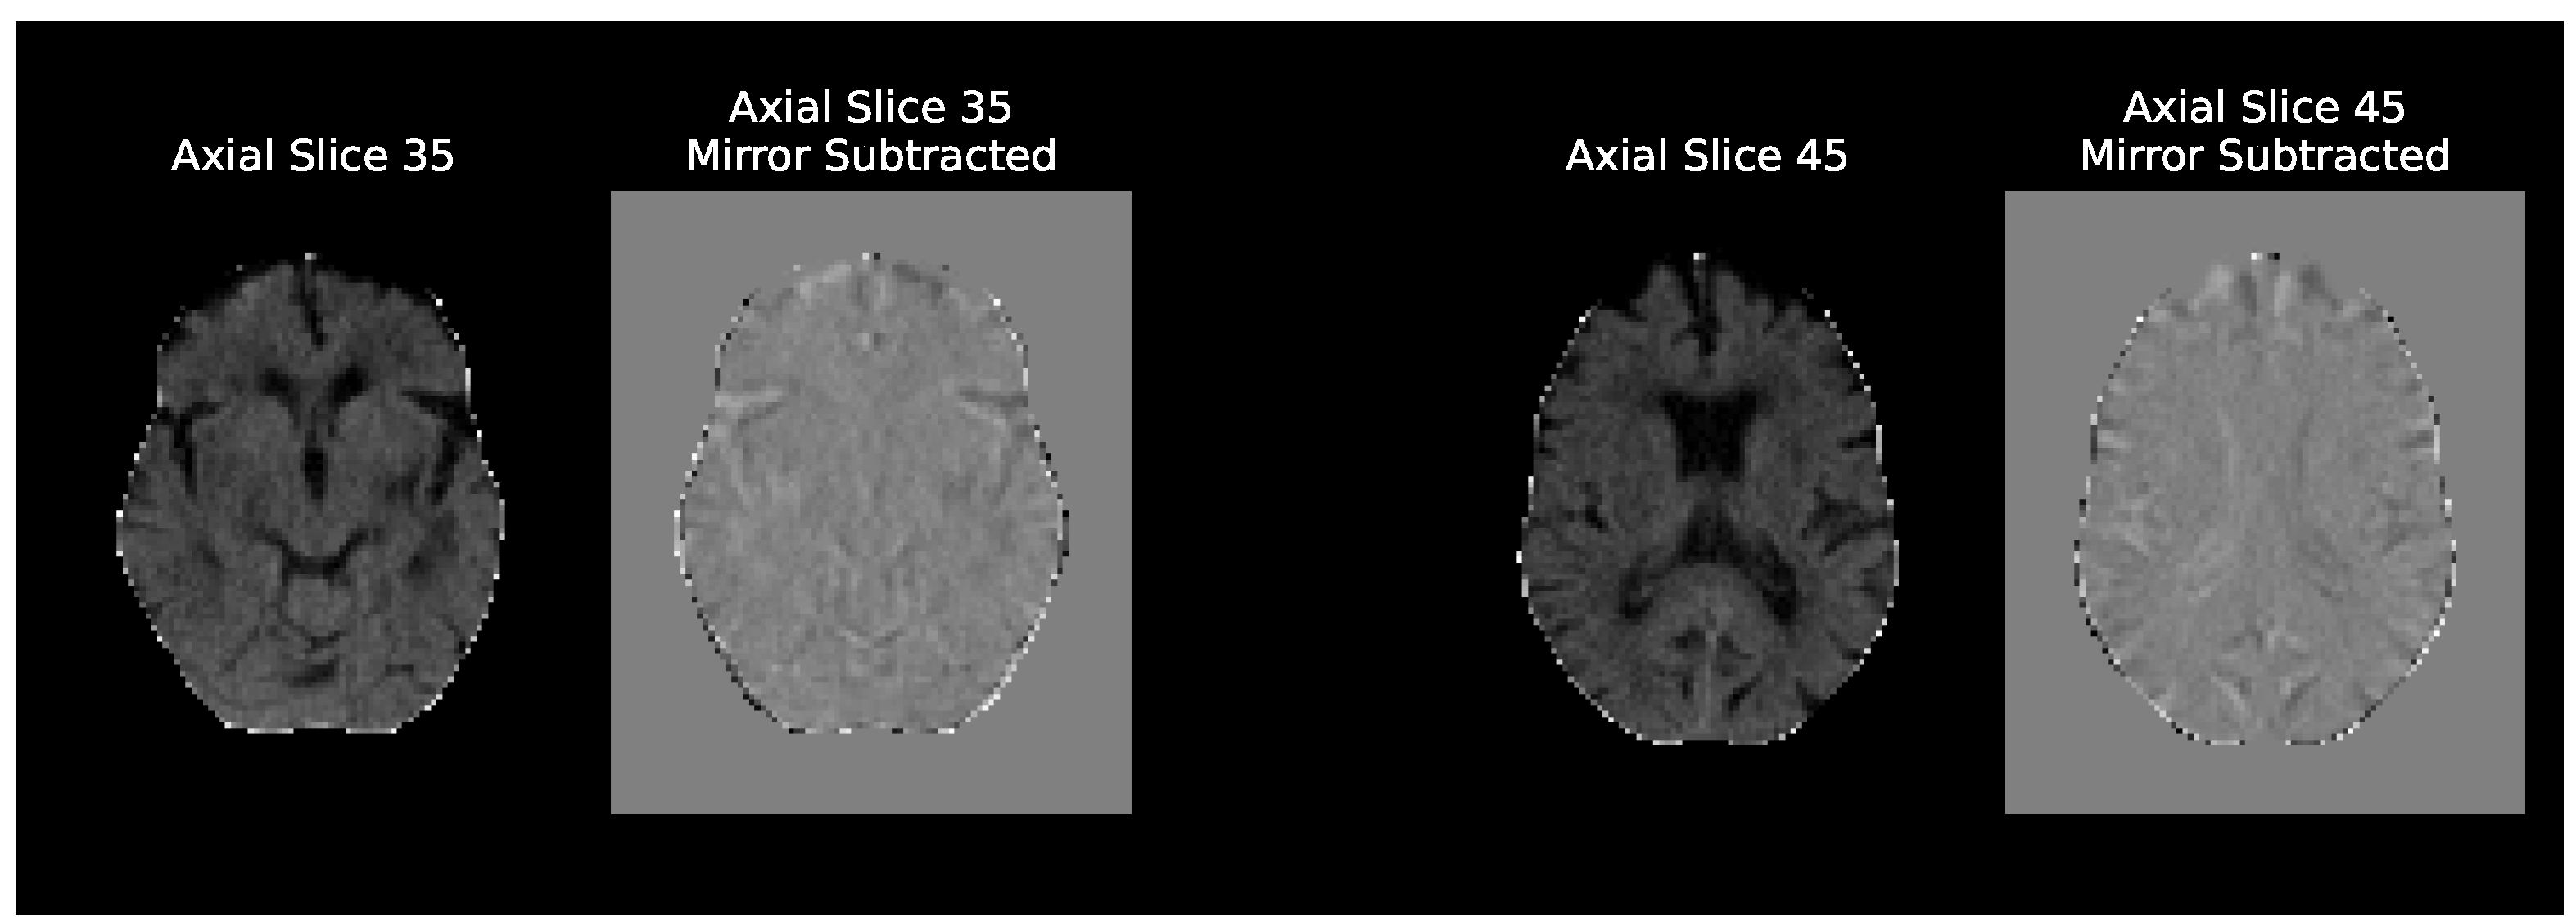

3.2. CT Preprocessing